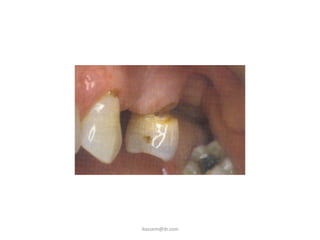

Displacement of the tooth

into:

-soft tissues

-maxillary sinus

-beyond the pharynx

Root Displacement

• Mandibular Canal

• Lingual Pouch

• Infratemporal Space

• Maxillary Sinus